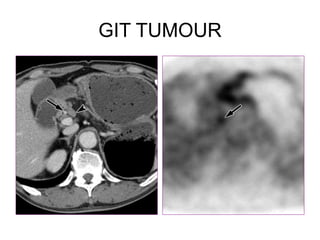

GIT TUMOUR

Diagnosis?